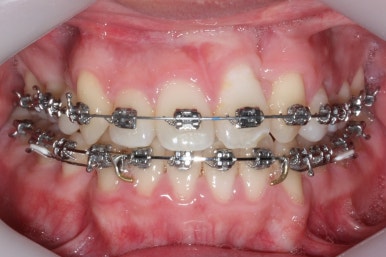

부산구순구개열 키다리아저씨치과에서 교정치료 하신지 1년여만에 드디어 앞니는 거꾸로 넘어왔고, 윗니들도 상당히 많이 가지런해졌습니다.

이 뽑은 자리도 상당히 많이 줄어든 것을 볼 수 있고, 이제는 정상적인 포개짐이 만들어졌습니다.

아래 치열은 거의 완료가 되었네요.

이 뽑은 자리도 다 없어졌고요. 대신 윗니는 어금니쪽에 약간의 틈과 기울어진 경사 등등 디테일한 조절을 계속해 나갑니다.

가장 최근의 사진입니다.

아직 치료 종료는 안되었으나 약간의 조절을 더하면 치료를 마무리할 수 있을 것 같습니다.

물론 윗니 한 쪽은 작은 앞니가 없고 한 쪽은 작은 어금니가 없기 때문에 중앙선이 100% 일치하지는 못하겠지만 기능적으로나 미적으로나 매우 개선되었음은 틀림없습니다.